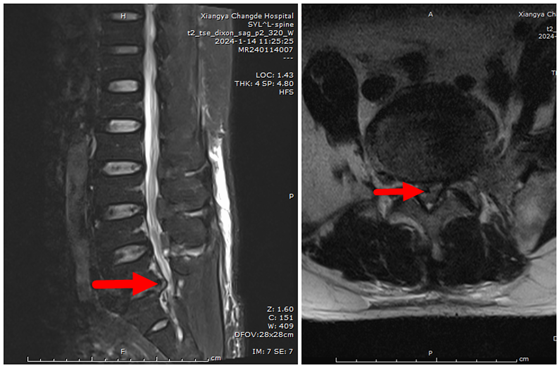

术前磁共振提示L5/S1节段椎间盘突出,相应平面椎管狭窄